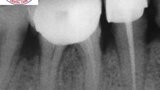

Fig.1a: Pre-op radiograph taken by the referring dentist.

Fig.1b: Pre-op radiograph taken by the author in relation to tooth #46 (January 2019).